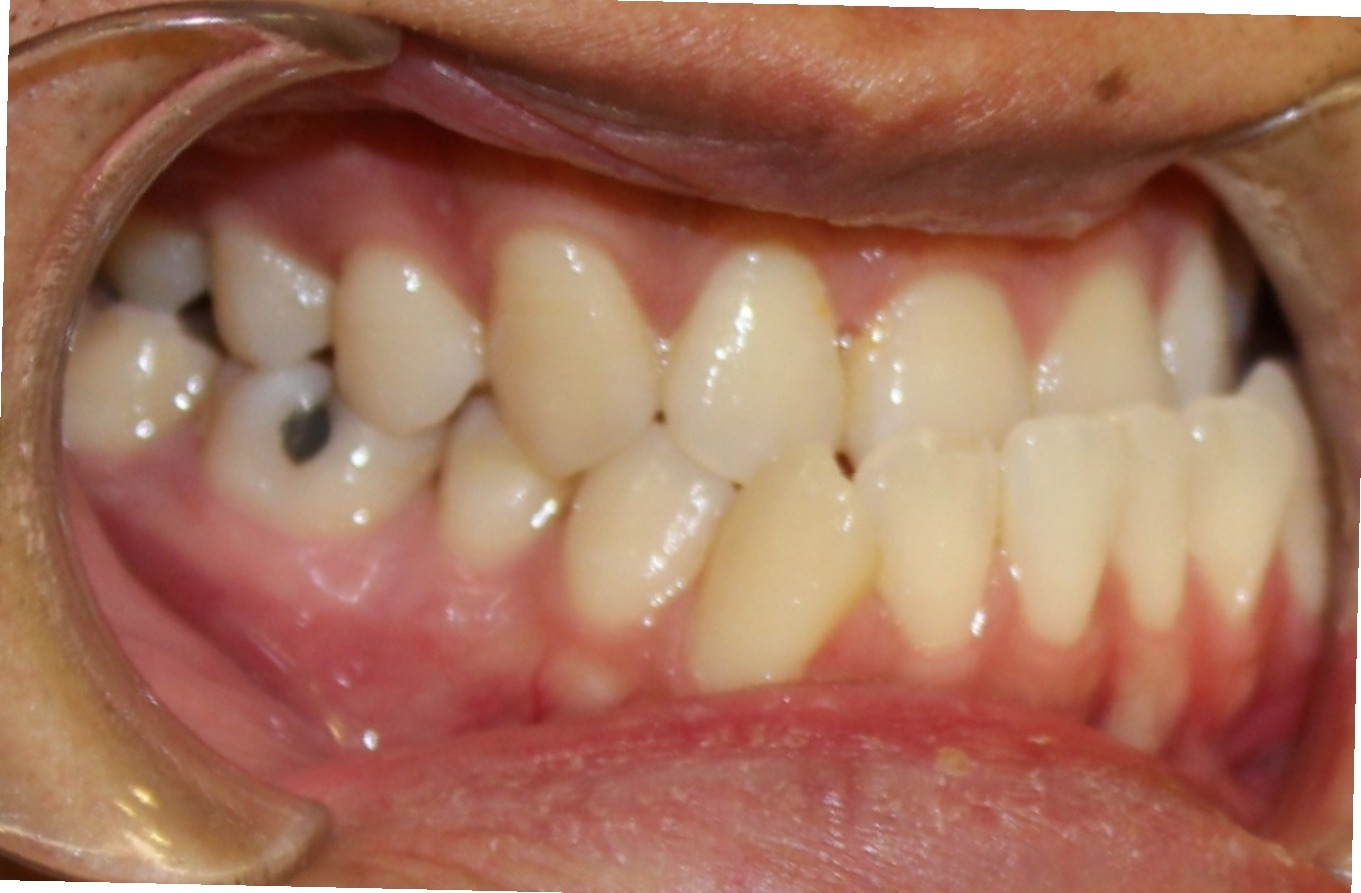

From yangorthodontics.com

One of our patients at Yang Orthodontics had a severe underbite Orthodontics And Orthognathic Jaw Surgery The length of your actual surgery is approximately two to three hours per jaw. Jaw surgery, also called orthognathic surgery, is surgery that helps align your upper jaw (maxilla) and lower jaw (mandible). A guide for patients considering orthodontics and jaw surgery (orthognathic treatment). They may include orthognathic, which refers to the causes and treatment of bones. Orthognathic surgery is. Orthodontics And Orthognathic Jaw Surgery.